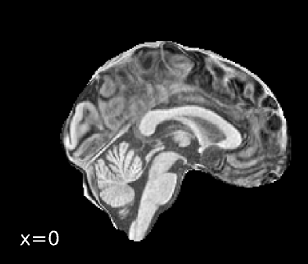

Brain surfaces were reconstructed usingrecon-all[FreeSurfer 7.3.2,

RRID:SCR_001847, @fs_reconall], and the brain mask estimated

previously was refined with a custom variation of the method to reconcile

ANTs-derived and FreeSurfer-derived segmentations of the cortical

gray-matter of Mindboggle [RRID:SCR_002438, @mindboggle].

A T2-weighted image was used to improve pial surface refinement.